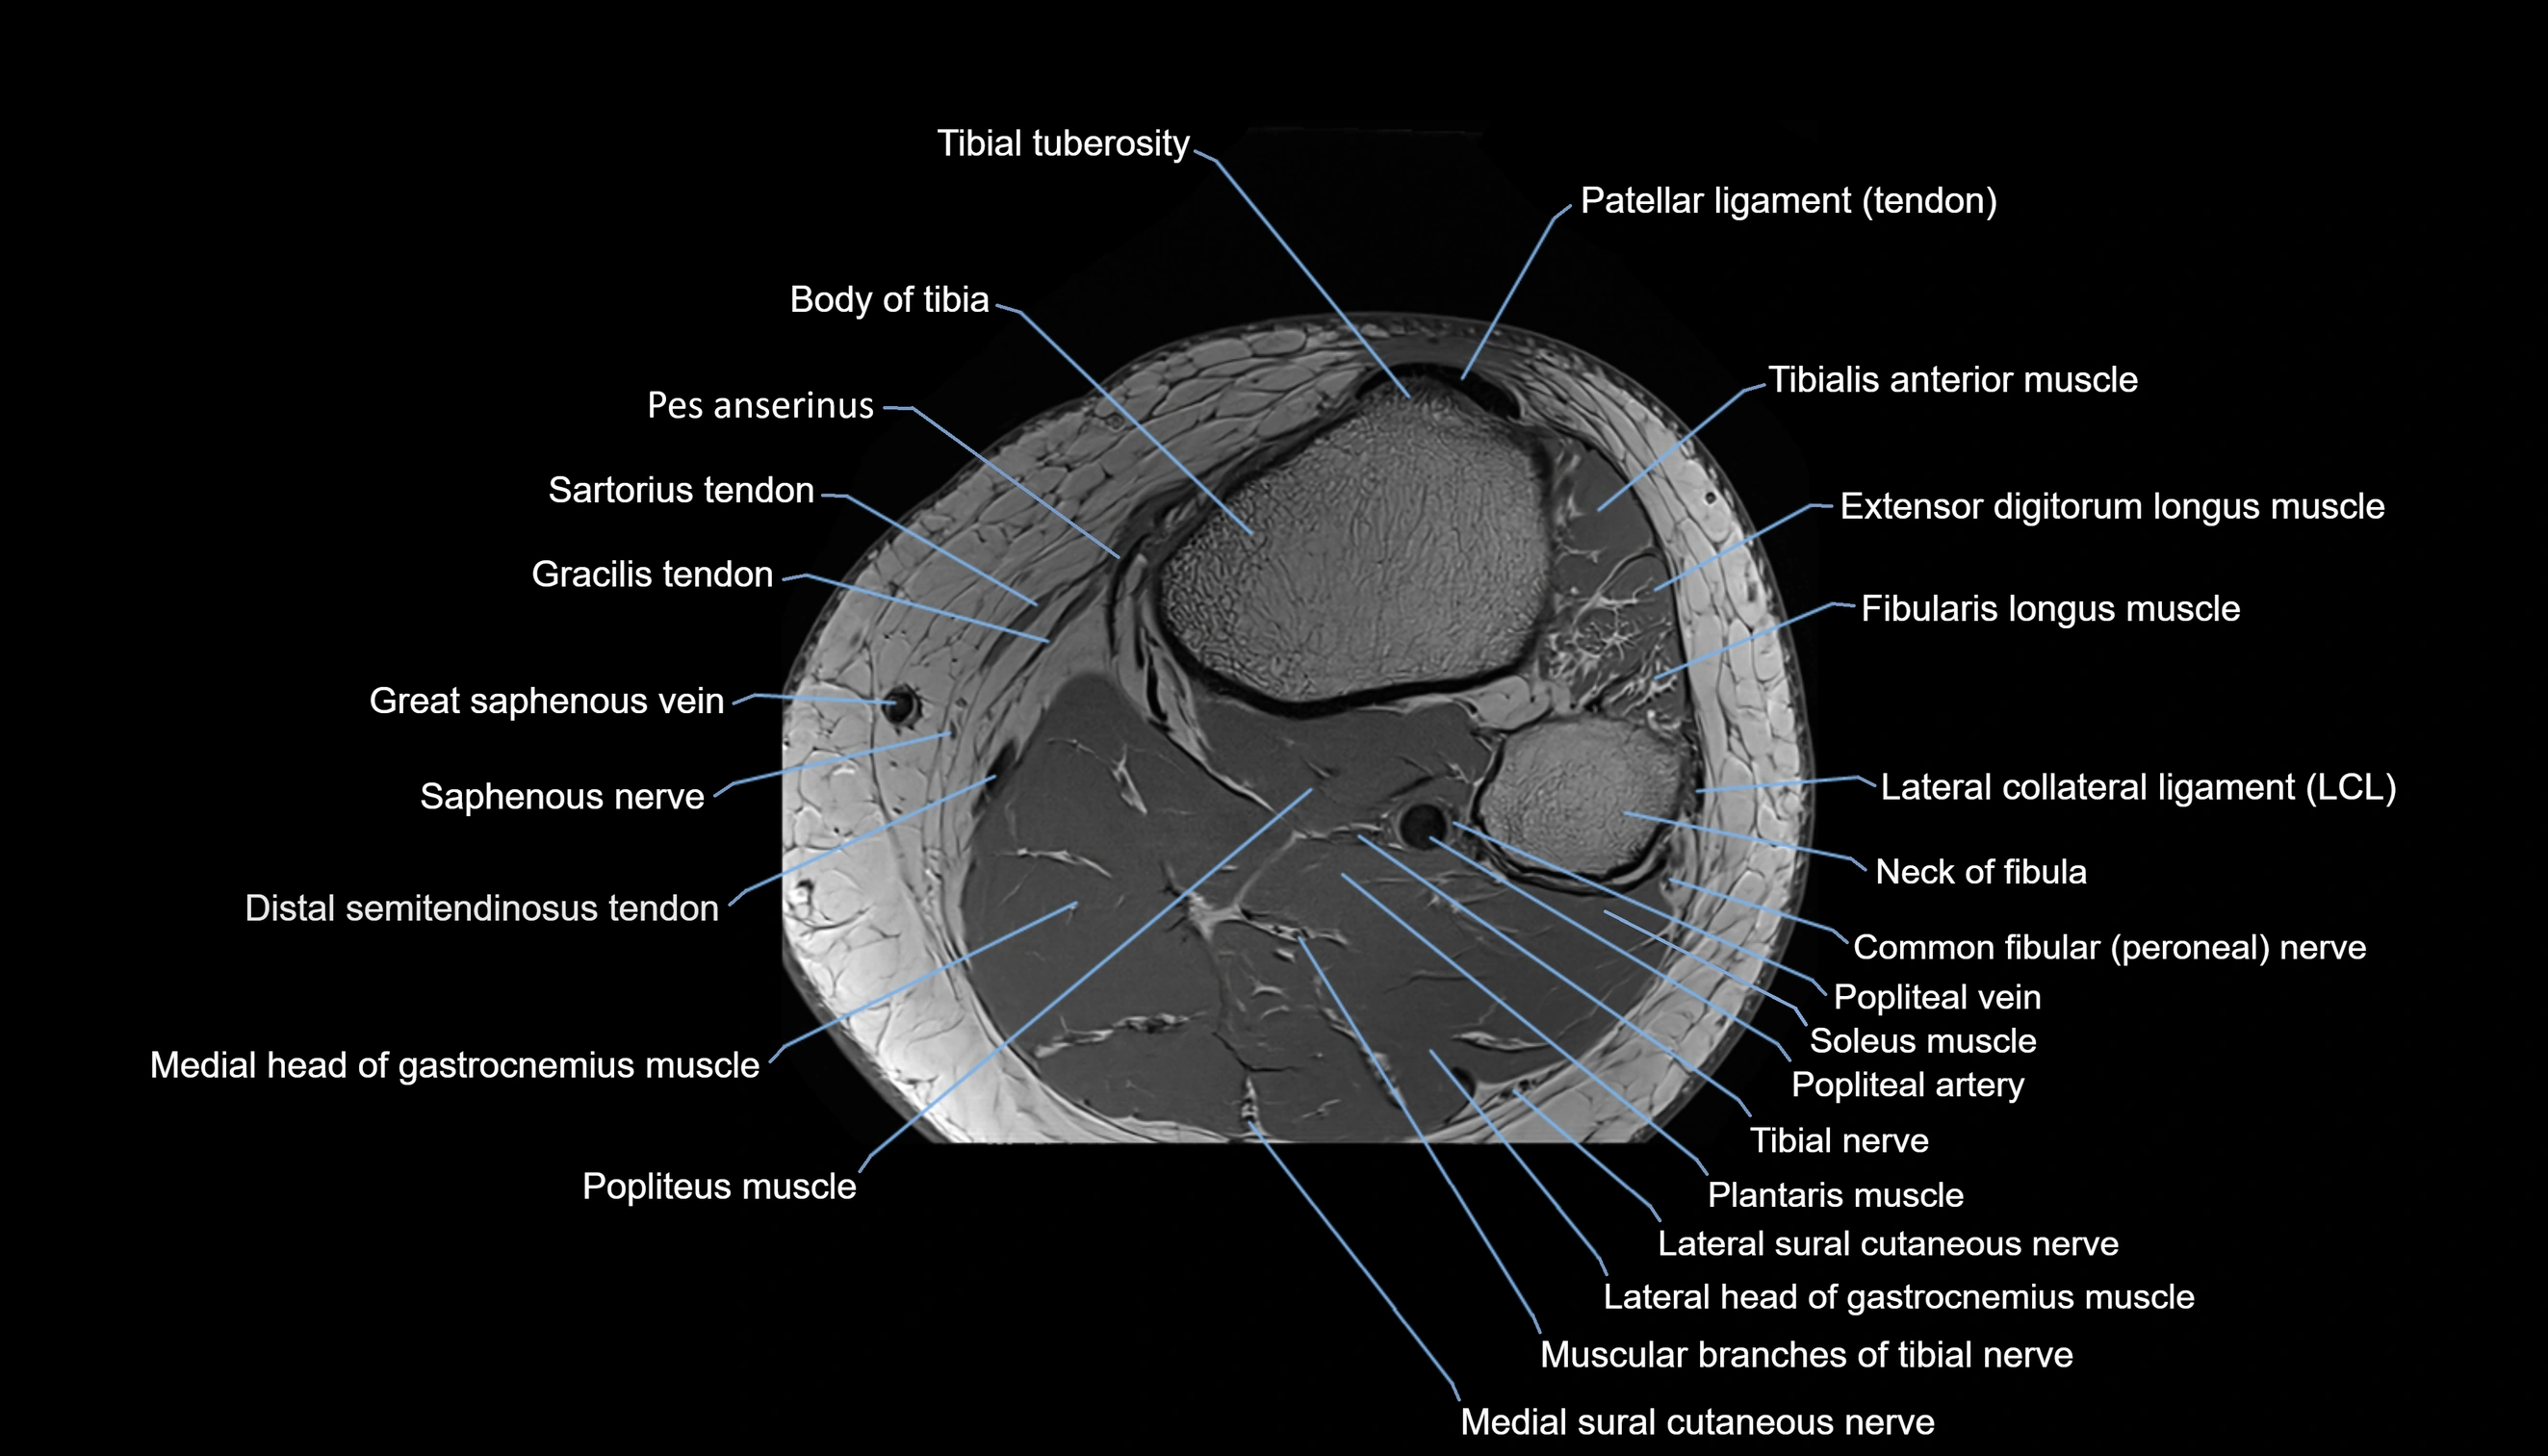

- Body of tibia

- Common fibular nerve

- Infrapatellar branch of saphenous nerve

- Lateral sural cutaneous nerve

- Medial sural cutaneous nerve

- Muscular branches of tibial nerve

- Neck of fibula

- Popliteal artery

- Popliteal vein

- Popliteus muscle

- Soleus muscle

- Tibial nerve

- Tibial tuberosity

- Tibialis anterior muscle

- great saphenous vein